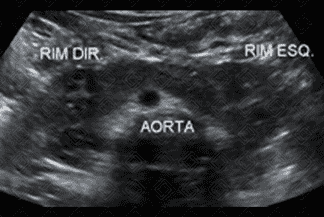

Texto alternativo para a imagem Figuras 1, 2, 3 e 4. Créditos: Dra. Elazir Mota - Rio de Janeiro/RJ

Descrição das figuras 1, 2, 3 e 4: Ultrassonografia das vias urinárias evidenciando rins em ferradura. Observe que o rim esquerdo é menor e apresenta alteração rotacional. Ao avaliar a linha média, anteriormente à aorta, observa-se a fusão dos polos renais inferiores.

• Ultrassonografia das vias urinárias: N ota-se fusão dos pólos inferiores dos rins na linha média, anteriormente à aorta (como nas imagens radiológicas). Sempre avaliar bexiga e sistema coletor, buscando por sinais de dilatação, já que nestes casos é comum a dificuldade de drenagem nas pelves renais;